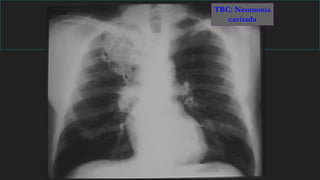

Signos radiológicos principales

Absceso

Condensación

basal cavitada

(AP)

TBC: Neumonía

cavitada